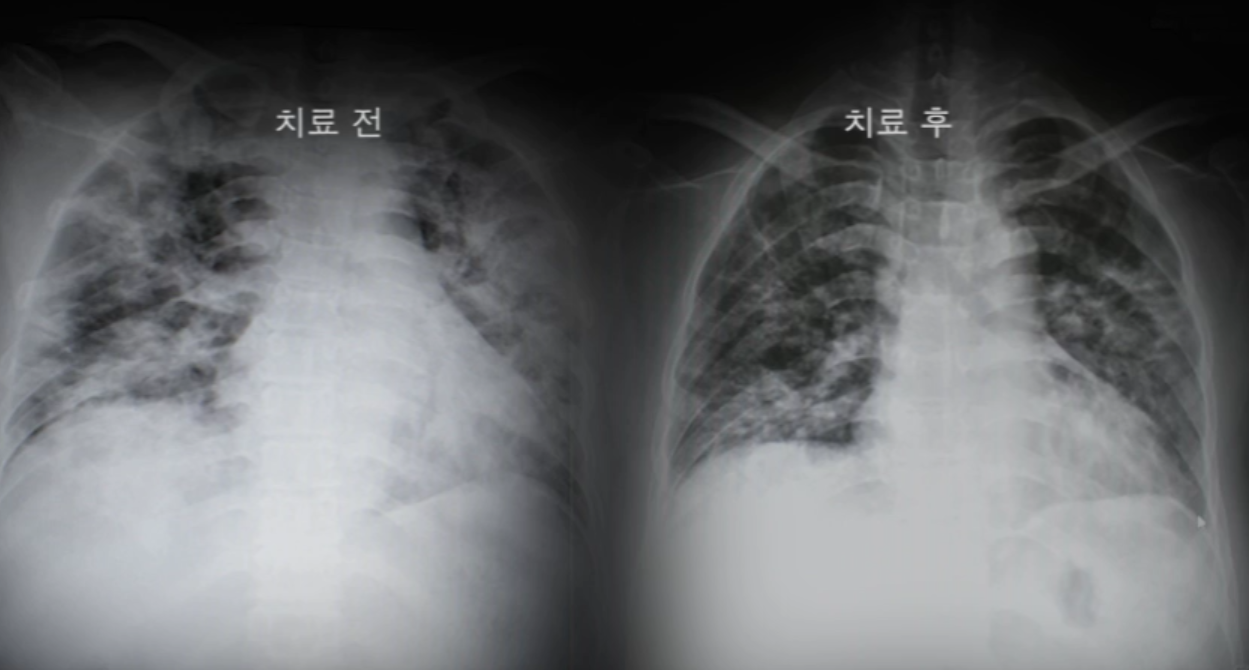

■코로나19 완치 후 계속해서 망가져 가는 폐.

질병관리청과 롱코비드 공동연구를 진행 중인 세브란스병원 감염내과 최준용 교수는 코로나19 자가격리 해제 이후 폐 손상의 위험성을 강하게 경고했다. 바이러스 전파력이 줄어든 이후에도 염증반응은 폐에서 전신으로 계속해서 퍼져나가기 때문이다. 최준용 교수는 심각한 폐 손상으로 폐 이식을 받게 되는 롱코비드 환자가 적지 않다고 말하며 코로나19 자가격리 해제 이후 적어도 2주 이상은 호흡기 건강상태를 잘 체크해야 한다고 전했다.